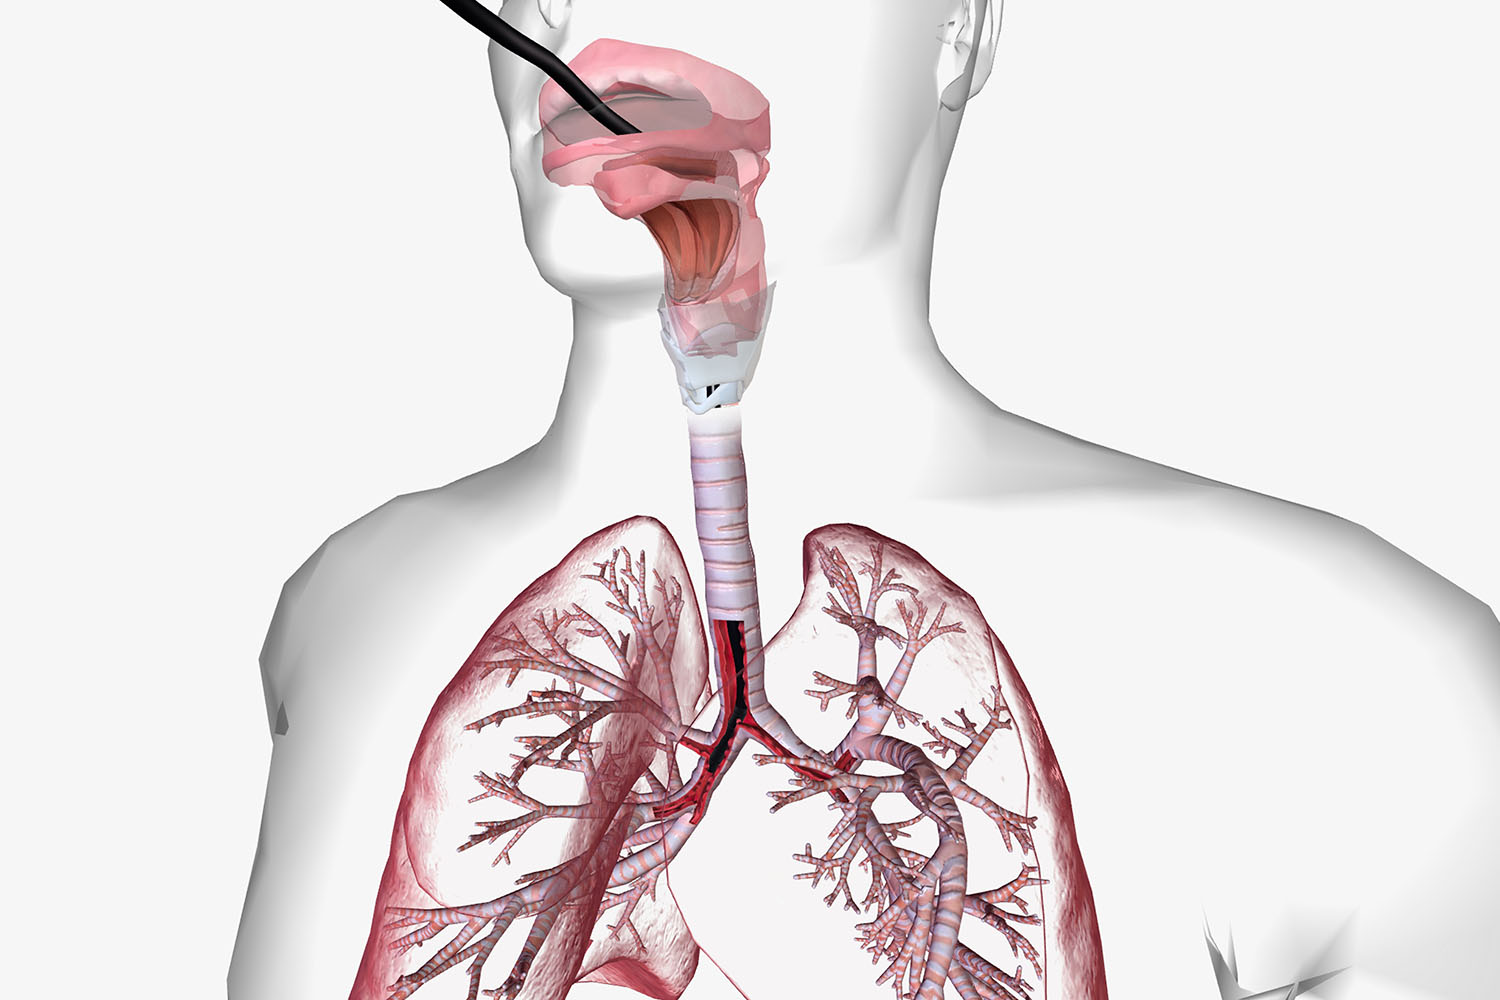

Minimally invasive procedure to examine the airways, collect samples, and assist in the treatment of respiratory disorders.